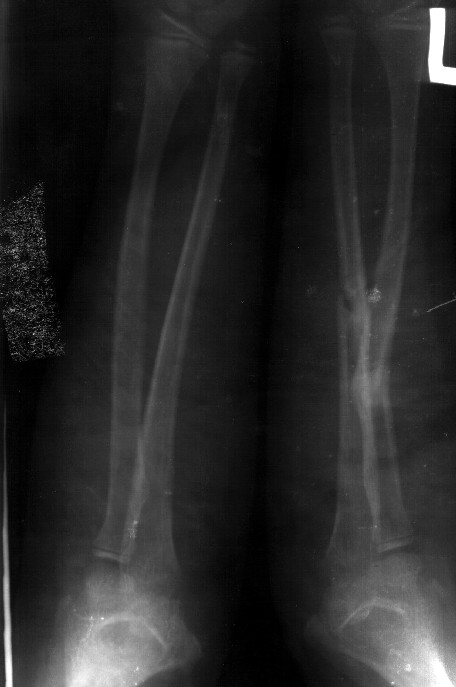

СМ> Сделал симметричные снимки с максимальной супинацией и пронацией при

СМ> согнутом предплечье в 90 град. Объем ротационных движений 90-100 град.

Снимок один сделан с супинацией, второй - оба предплечья в одинаково нейтральном положении. то есть по этим снимкам объем ротационных движений не оценить. Снимко в двух проекциях лучше и делать в среднем положении между пронацией и супинацией, то есть обе проекции в однм и том же положении, когда линия, проходящая через шиловидные отростки, идет в плоскости головки. Прошу прощения за усложнение простых вещей.